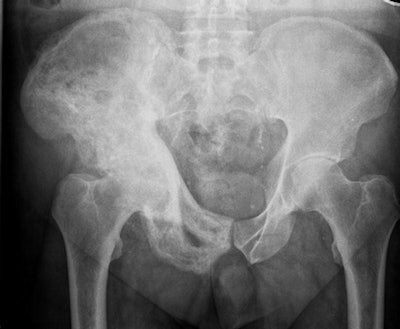

Researchers chose 300 musculoskeletal and chest x-rays for rapid reporting and compared the performance of a commercially available AI tool with that of 26 radiologists who had passed the Fellowship of the Royal College of Radiologists (FRCR) exam the previous year.

When uninterpretable images were excluded, the AI candidate achieved an accuracy of 79.5% and passed two of 10 mock FRCR exams, while the average radiologist achieved an accuracy of 84.8% and passed four of 10 mock examinations, noted lead author Dr. Susan Cheng Shelmerdine, PhD, a consultant pediatric radiologist at Great Ormond Street Hospital for Children NHS Foundation Trust in London, and colleagues.

The sensitivity for the AI candidate was 83.6% and the specificity (ability to correctly identify patients without a condition) was 75.2%, compared with 84.1% and 87.3% for the radiologists.

The AI candidate was Smarturgences v1.17.0, developed by French AI company Milvue and marketed since February 2020. It is used clinically in over 10 European hospitals and has been trained to assess MSK radiographs for fractures, swollen and dislocated joints, collapsed lungs, etc.